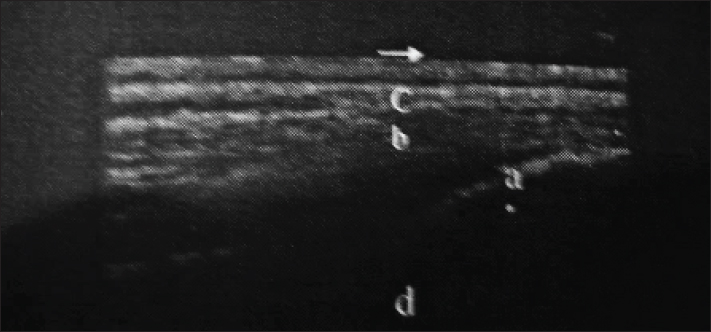

Supraspinous and sacroiliac ligament ultrasonography in transverse and longitudinal planes were performed using a portable ultrasound machine and a 7.5-MHz linear array transducer. A stand-off water-bag cushion was used to improve the resolution of superficial structures. Three sound horses were also scanned US at the same locations for comparison (Fig. 3).

Fig. 3. Longitudinal ultrasongraphy at the sacro-iliac region (a-the dorsal sacroiliac ligament, b-longissimus dorsi tendon, c-gluteal fascia, and d- sacral tuber).